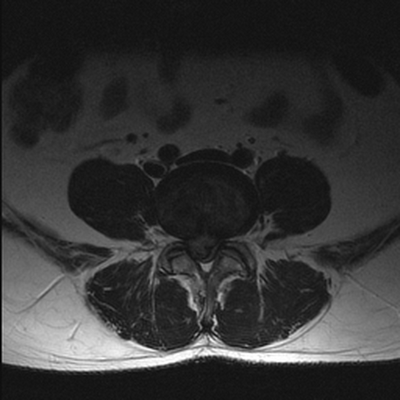

МРТ позвоночника. Аксиальная Т2-взвешенная МРТ. Нормальный срез через дугоотростчатые суставы.